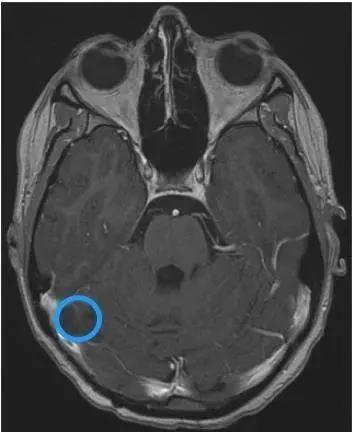

術(shù)前影像顯示腫瘤侵犯右側(cè)橫竇。C冠狀位影像顯示右側(cè)小腦半球腫瘤侵犯右側(cè)橫竇。

當(dāng)檢查結(jié)果出來的那一刻,Cathy的父母如遭雷擊:她右側(cè)小腦半球有一個巨大占位:尺寸約5.6×5.0×3.4cm——宛如一顆雞蛋藏在腦中。第四腦室也變得狹窄,還出現(xiàn)了梗阻性腦積水,初步診斷為惡性髓母細(xì)胞瘤。

更棘手的是,腫瘤已侵犯右側(cè)橫竇,這是顱內(nèi)重要的靜脈回流通道,若手術(shù)中為了切除腫瘤而損傷橫竇,可能引發(fā)大出血、靜脈竇血栓等嚴(yán)重并發(fā)癥,甚至直接導(dǎo)致手術(shù)失敗。

術(shù)后影像顯示右側(cè)橫竇有一個小的殘余腫瘤。C顯示右側(cè)橫竇局灶性血流缺損。